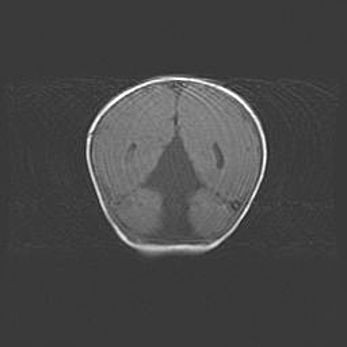

Церебральная ишемия II.

Возраст: 5 дней

Вес: 3400 г

Пол: женский

Окружность головы: 35 см

Срок гестации: 39 недель

Церебральная ишемия – это заболевание, характеризующееся недостаточностью (гипоксией) либо полным прекращением (аноксией) снабжения мозга кислородом по причине закупорки одного или нескольких сосудов. Это приводит к  что метаболическим расстройствам различной степени тяжести в тканях головного мозга, развитию коагуляционных некрозов и гибели нейронов.